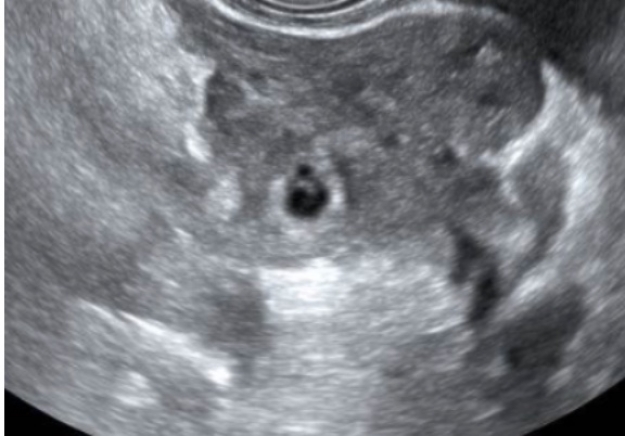

Bedside point of care ultrasound is performed and reveals the following images (shown below). What’s the diagnosis? Scroll down for answer.

Transvaginal US - Right uterus/adnexa

Answer: Ruptured Cornual (ie Interstitial) Ectopic Pregnancy

For example, our patient had what LOOKED to be a gestational sac in the uterus, but it was actually a pseudogestational sac (see mid uterus view above). Upon further investigation, we found the complex adnexal mass in addition to the intrauterine ‘sac’.